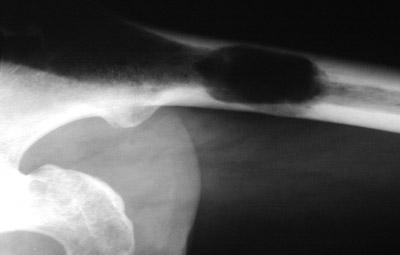

![]() | The rounded lucency seen here in the upper shaft of the femur is a plasmacytoma, a collection of plasma cells. In another case below, the lytic distal femoral lesion is more subtle. Since these patients had other lesions, this is not a solitary plasmacytoma, but multiple myeloma. His total serum immunoglobulin level was greatly increased, with an IgG "spike" seen on serum protein electrophoresis and bands of IgG and kappa on immunoelectrophoresis of serum. |